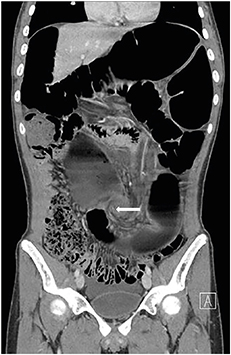

A previously healthy 16-year-old boy with stable vital signs presented with vomiting, diarrhea, distension, and abdominal pain for 4 days. On physical examination, he had abdominal distension with mild abdominal tenderness but without rebound tenderness, and a subtle metallic bowel sound. Laboratory test results were normal. An abdominal radiography revealed a dilated sigmoid colon on the left quadrant (Fig. 1). An abdominal computed tomography (CT) revealed a marked distension of the gas-filled sigmoid colon with twisting of the mesenteric vessels, confirming SV (Fig. 2). A rectal tube was inserted to decompress the volvulus (Fig. 3). He remained asymptomatic thereafter, and discharge was requested. At 2 and 7 months after his initial attack, he was readmitted to the emergency department with the same complaints. Subsequent examinations confirmed the recurrence of SV. The SV was successfully decompressed by means of a rectal tube. His parents again refused surgical treatment; however, 9 months after the first attack, he underwent laparoscopic-assisted sigmoid colectomy. We use a 12 mm port above the umbilicus, a 5 mm right upper quadrant port, a 5 mm left sided port, and a 12 mm right lower quadrant port & left lower quadrant, typically placed 2 fingerbreadths medial and 2 fingerbreadths cephalad to the anterior superior iliac spine. After mobilization of the sigmoid colon, the colon was transected at the rectosigmoid junction with an endolinear stapler (SigniaTM Stapling System; Medtronic, Minneapolis, MN, USA). The umbilical incision was extended. The divided sigmoid colon was exteriorized, and the redundant part was resected. A sigmoid colon section of 34 cm was resected; end-to-end colorectal anastomosis was performed intracorporeally using a circular stapler (ECHELON CIRCULARTM 25 mm Powered Stapler; Ethicon, Bridgewater, NJ, USA). A seromuscular biopsy specimen from the distal colon submitted for histopathologic examination showed normal ganglion cells. On postoperative day 3, he was started on water intake; subsequently, eating progressed successfully. He was discharged without complications on postoperative day 10.

Fig. 1

Abdominal X-ray showing a dilated sigmoid colon on the left quadrant with the characteristic coffee bean sign.